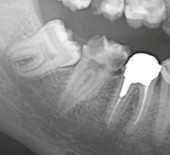

レントゲンによる虫歯の深度の把握をします。また、熱いものや冷たいものが沁みていないか神経の状態の把握をします。